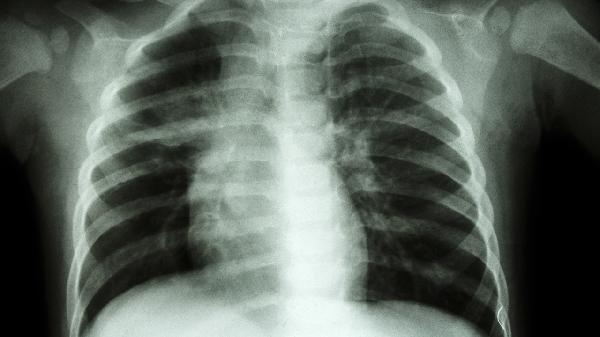

每3-6个月进行胸围测量和肺功能检查,儿童患者需监测骨龄发育情况。拍摄系列胸片对比肋弓角度变化,重度进展者需评估是否合并脊柱侧弯。生长发育期患者建议每季度评估营养状况。